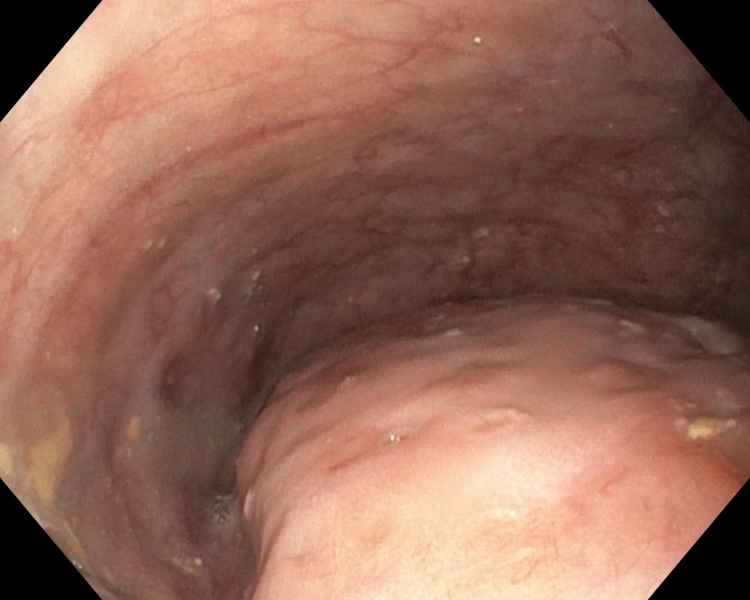

Back to Black

Fotografia